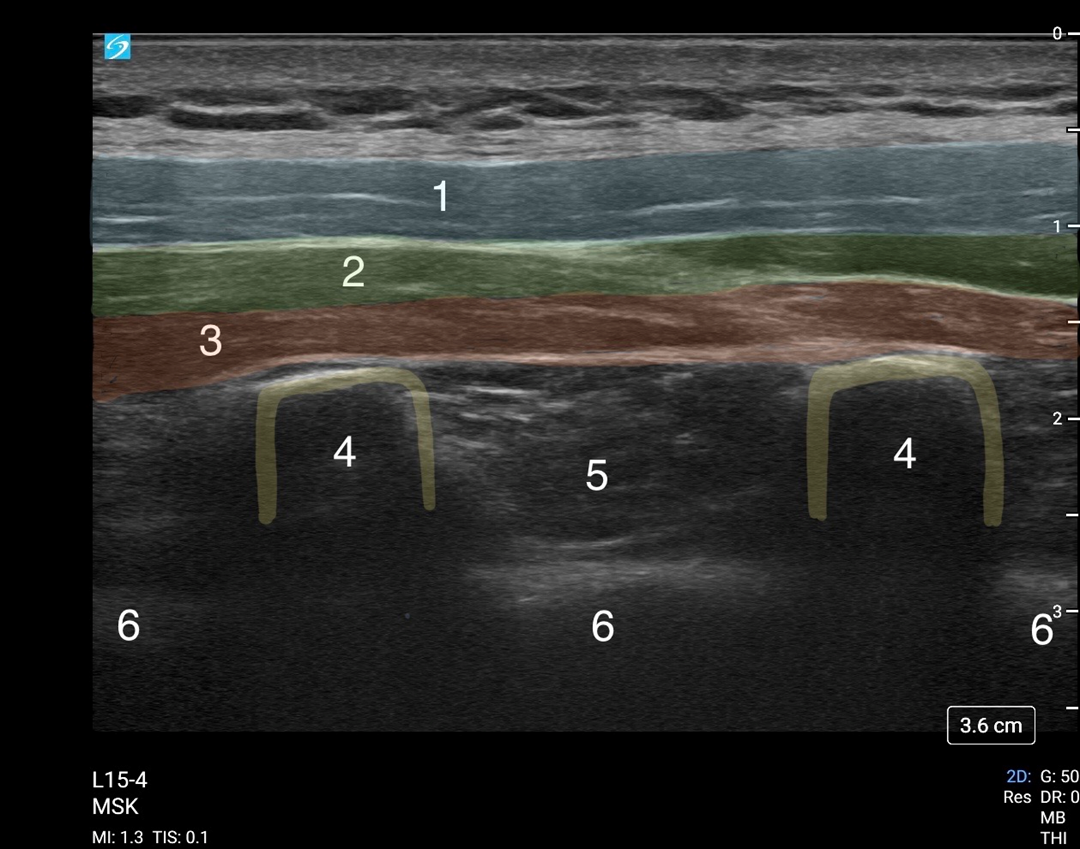

ESP Block Anatomy Image

1. Trapezius Muscle

2. Rhomboid Muscle

3. Erector Spinae Muscle

4. Transverse Process

5. Paravertebral Space

6. Pleura